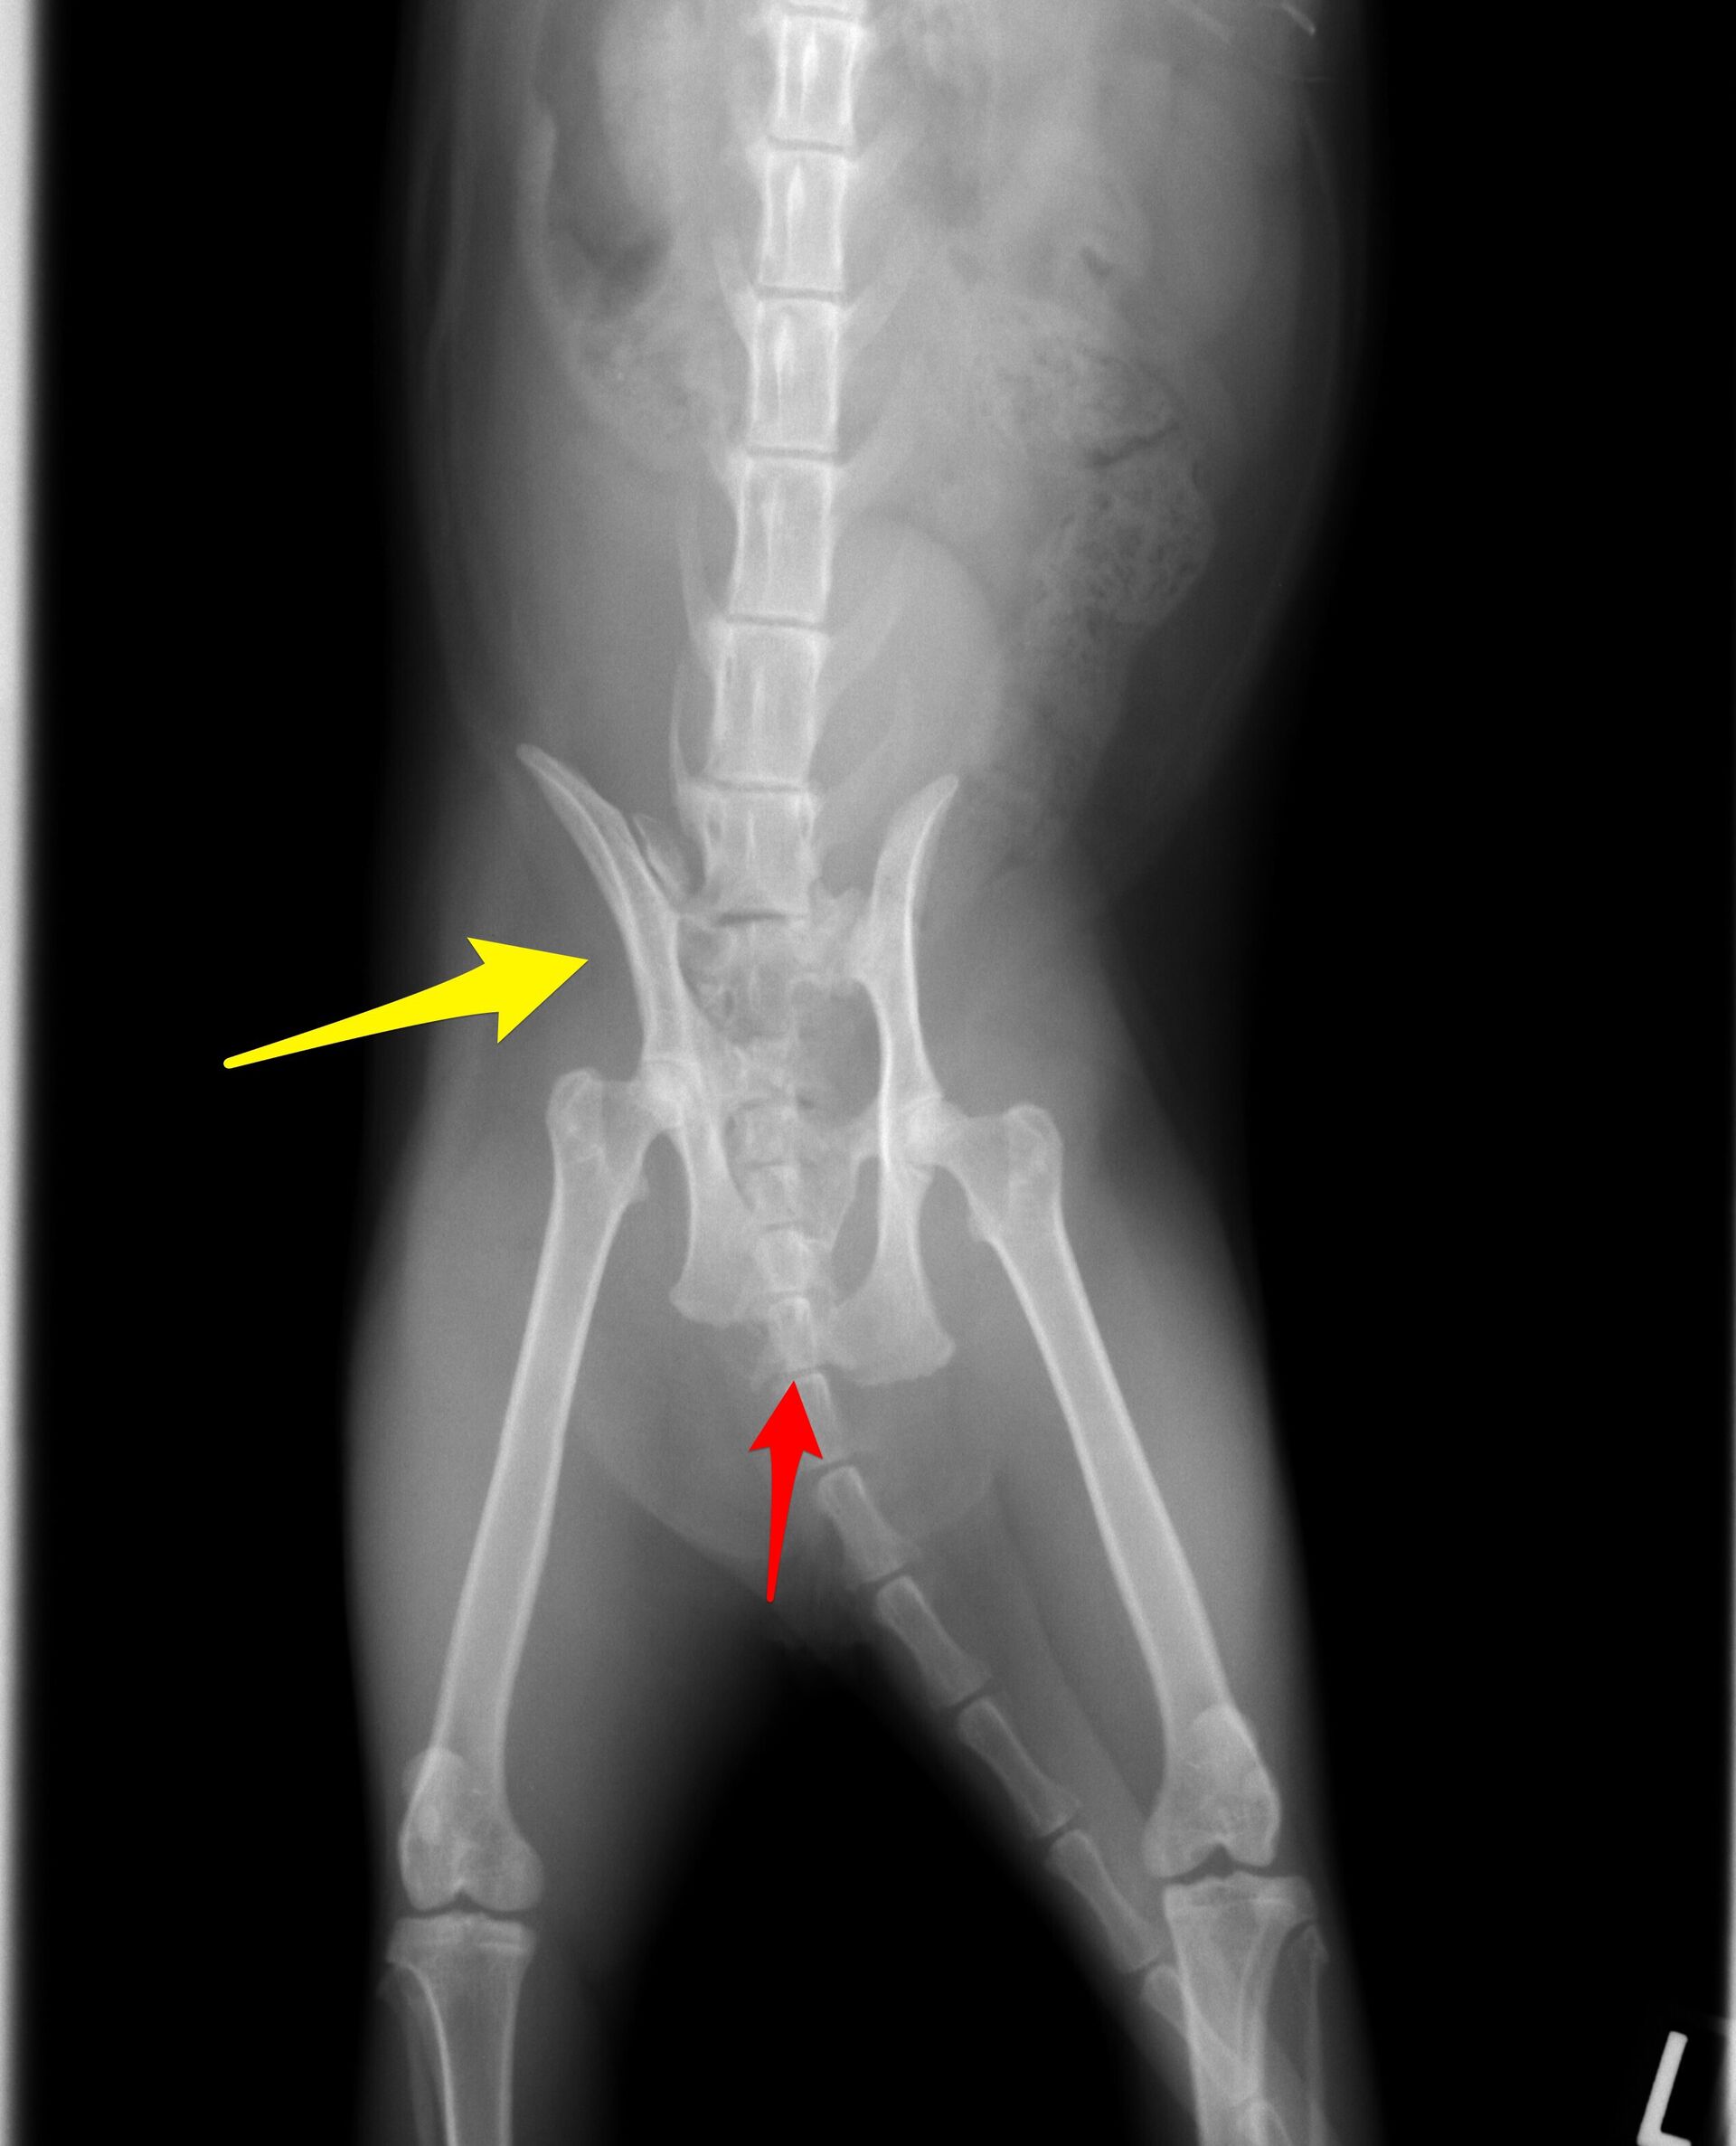

レントゲンを撮ったところ、下の写真のように骨盤を骨折していました。

今回の骨盤骨折は、仙腸関節が(黄色矢印)外れてしまっているのと

恥骨が骨折(赤色矢印)しています。仙腸関節は腸骨と仙骨(背骨)の

関節で言わば背骨と後肢を固定している所で、歩行する上で大変重要な

役目を担っています。整復しなくても歩行は何とかなる場合もあるのですが、

骨盤腔が狭くなることで便の通りが悪くなり、ひどい便秘になることは

ほぼ間違いありません。